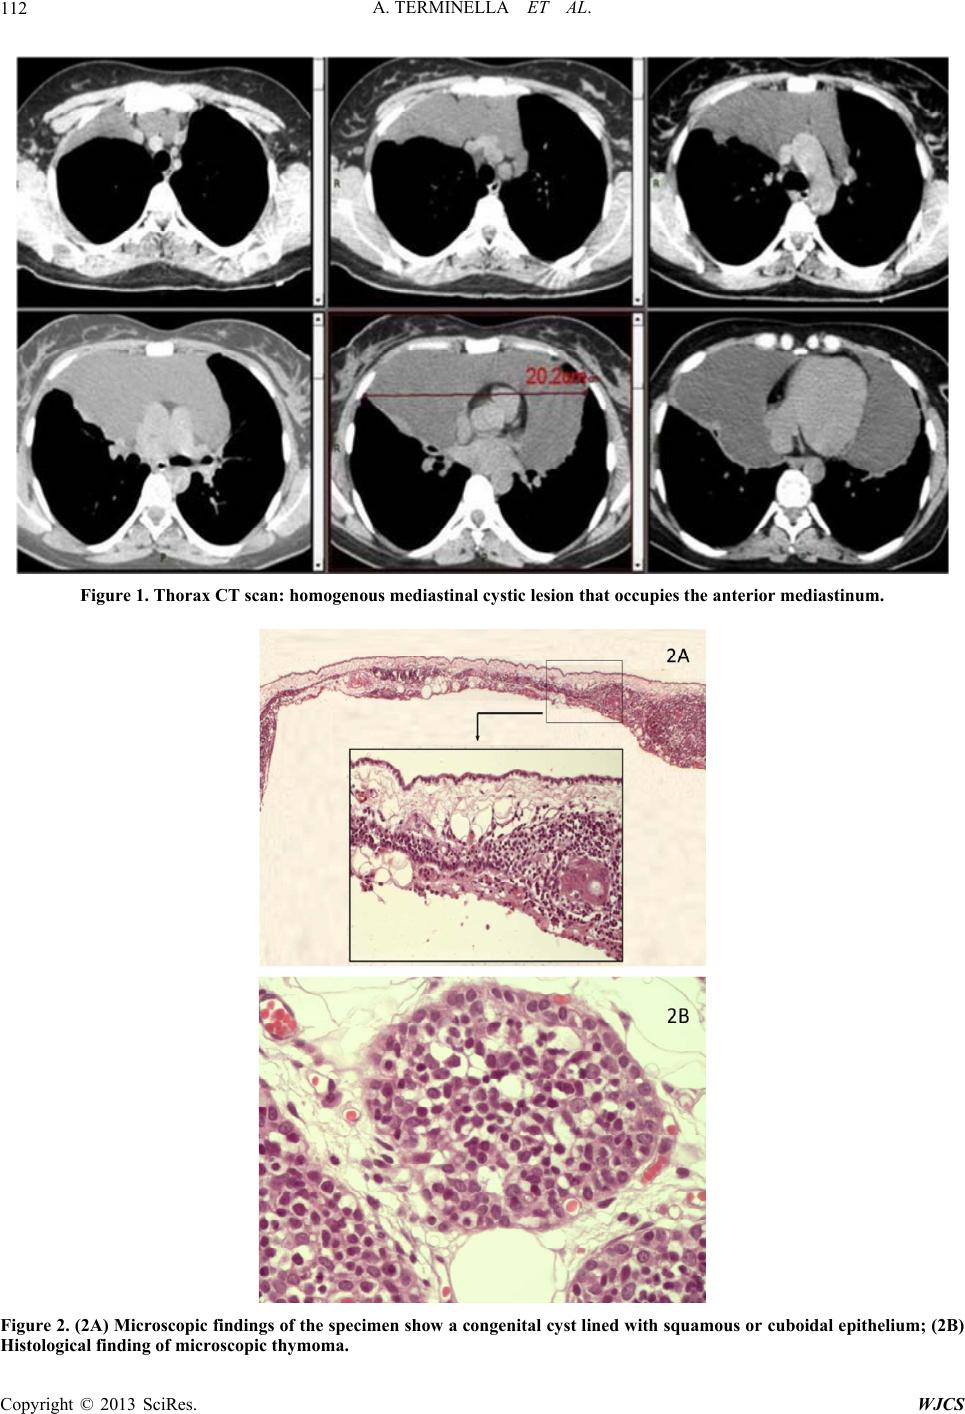

From www.scirp.org

Huge Congenital Thymic Cyst with Microscopic Thymoma Thymic Cyst Vs Thymoma They are usually asymptomatic and mostly occur in. Although thymic cysts are often reported,. However, the data from which we can draw this. Computed tomography is the imaging modality of choice for evaluating thymoma and can help distinguish thymoma from other anterior mediastinal. Cystic changes in thymomas are differentiated by the lack of epithelium on the cyst wall. Lymphoid follicles. Thymic Cyst Vs Thymoma.

Huge Congenital Thymic Cyst with Microscopic Thymoma Thymic Cyst Vs Thymoma Lymphoid follicles in thymic follicular hyperplasia (caveat: Anterior mediastinal masses include a wide spectrum of malignant and benign pathologies with a large percentage. However, the data from which we can draw this. Cystic changes in thymomas are differentiated by the lack of epithelium on the cyst wall. The objective of this study was to develop a clinical model for. Computed. Thymic Cyst Vs Thymoma.